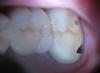

Отсутствовала левая верхняя шестерка. установили мост. Долго подгоняли под прикус,обтачивали жевательную поверхность.Жевательную поверхность седьмого зуба протерли до блестящего металла.У меня вопрос: насколько травматична будет съёмка этой конструкции под пятым и седьмым зубом вкладки? продолжать ли иметь дело с этим врачом? неужели нельзя изготовить точную коронку и не стачивать жевательную поверхность во рту у пациента?

post-17503-1297373100_thumb.jpgpost-17503-1297373135_thumb.jpg